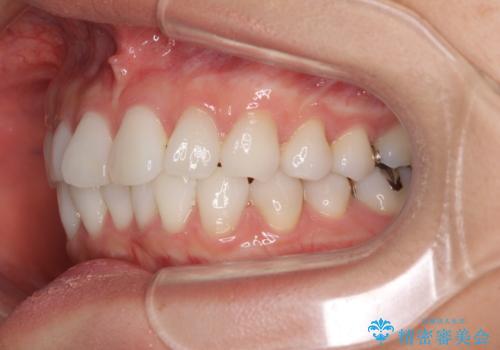

- 前歯のデコボコを気にして来院された患者様です。

海外に留学をされており、卒業後はしばらく日本にいるものの、再び就職のため出国するとのことでした。

定期的に日本に戻ってくる予定であるため、来院頻度の少ないインビザラインにて矯正治療を行うこととしました。

歯列不正が軽度であり、インビザラインの装着時間を遵守してくださったため、日本と海外を行き来しながらも2年弱でしっかりと仕上げることができました。